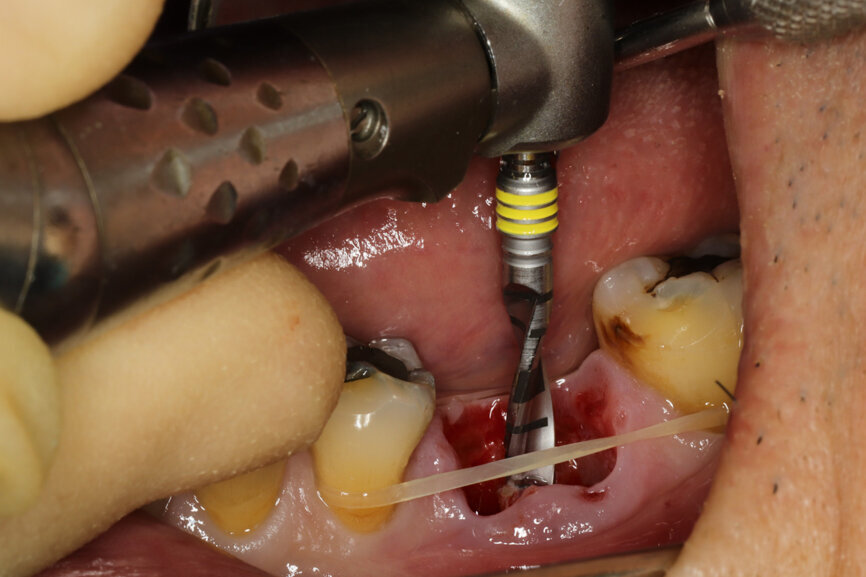

Fig. 6: Osteotomy with the ⌀ 2.2 mm drill.

It was possible to verify solid interradicular bone availability (Fig. 5), extending further the limits of the root apices and allowing for a centrally oriented osteotomy. The implant bed preparation started with the use of a needle drill at 800 rpm, followed by the ⌀ 2.2 mm and ⌀ 2.8 mm drills (Figs. 6–10). The implant was placed with the use of ratchet and torque control, reaching the desired final position at a 50 N cm torque value (Figs. 11–13). The socket was then augmented with bovine-derived bone substitute impregnated with advanced platelet-rich fibrin (A-PRF) and finalised with sutures to keep the A-PRF application immobile, and a 3 mm healing abutment was placed (Figs. 14–17).